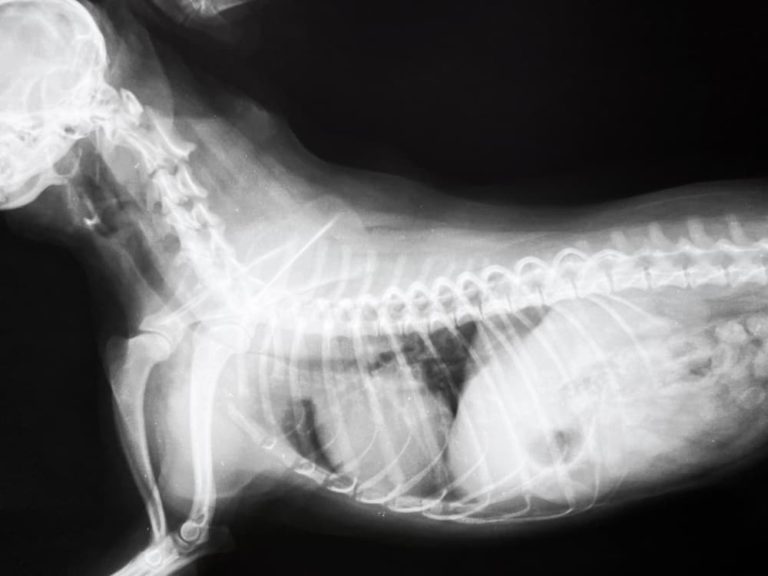

Tracheitis in dogs Symptoms, duration and treatment Dogsis Dog Coughing Sounds Like Wheezing Learn the causes and how to help your pup. Sounds like wheezing the characteristic wheezing sound that occurs when the dog is breathing is the most noticeable sign of wheezing in dogs. Most often heard as a dog exhales, a wheezing sound usually indicates that there is some sort of blockage of the air flow in either the trachea or. Dog Coughing Sounds Like Wheezing.